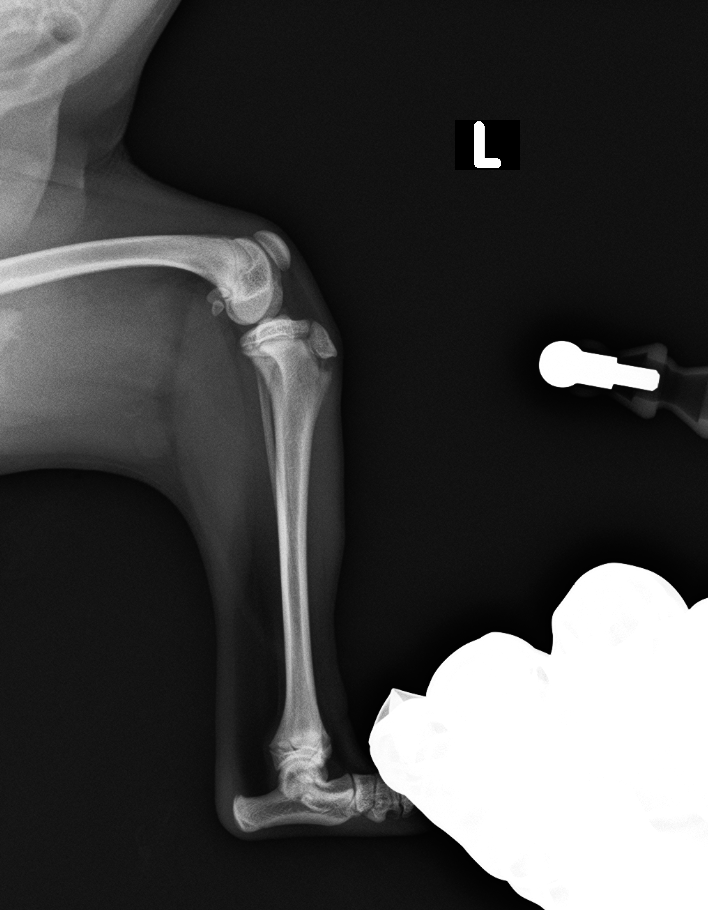

レントゲン検査より、脛骨粗面成長板の剥離

before